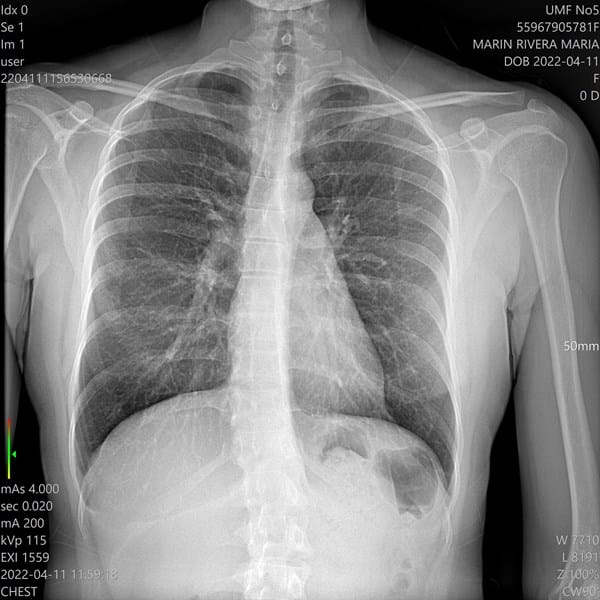

Formación ProfesionalUniversidadesMódulos Formativos carmen velasco el 22 sep. 22 De cuantos grados es la angulación Estas son radiografías de mi escoliosis De cuantos grados es la angulación de mi escoliosis necesito saber Seguir Siguiendo Dejar de seguir